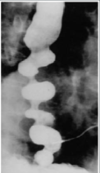

EXAME : ESOFAGOGRAFIA BARITADA. DIAGNÓSTICO DE ESPASMO ESOFAGIANO DIFUSO , CONSTRIÇÃO EM VÁRIOS PONTOS. TRATAMENTO : MAIS EFICAZ ESOFAGOMIOTOMIA LONGITUDINAL.